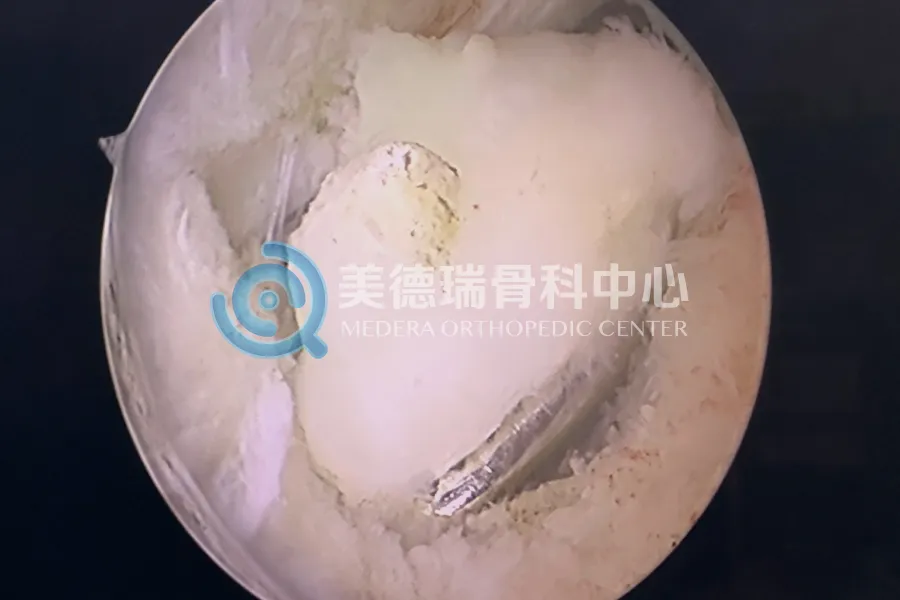

经过细致的查体与影像学评估,病因最终被锁定:一枚游离体卡在了髁间窝及后关节囊的深处,正是它构成了关节伸直的物理性阻挡。

这是一个非常典型的“机械性交锁”。我们可以把它想象成门轴里卡了一颗坚硬的石子。此时,如果无视这颗石子,盲目地用力推门(暴力锻炼),只会损坏合页,甚至破坏门框。对于这位患者而言,此前的每一次强行压腿,其实都是对关节软骨的一次磨损。

因为这枚游离体的位置太过“刁钻”。它躲在膝关节的后室,这里是常规关节镜手术的“视野盲区”,更是操作的“险滩”——狭小的空间紧邻腘窝的血管和神经束。在这样的位置进行手术,不仅需要精湛的技术,更需要极强的风险把控能力。

依托美德瑞骨科医生集团成熟的微创技术体系,张威医生专家团队为患者实施了关节镜下经后内侧入路游离体取出术。这一术式避开了大面积切开,在保护周围血管神经的前提下,通过微创通道直达关节后室,精准移除了那枚长期卡压关节的游离体。